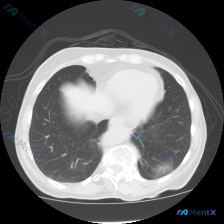

看到一个胸部CT肺窗的病例,整理了一下分析思路,和大家讨论。 病例信息: 患者提供的是肺窗胸部CT横断面影像,扫描层面在肺门下方的心室/心房水平。 影像表现: 1. 双肺透亮度基本对称,肺纹理走行自然,无大范围磨玻璃影或实变影。 2. 左肺下叶偏背侧、靠近肺门区域有一个类圆形病灶,直径约5-8mm,...

看到一个胸部CT病例,整理了一下思路分享给大家。 首先看病例资料:这是一张胸部CT横断面肺窗图像,扫描层面为胸廓中部,肺野透亮度基本对称,无明显弥漫性异常。重点发现是右肺下叶后基底段胸膜下有一个类圆形的微小实性结节,边缘较清晰,密度均匀,直径较小。周围肺实质无纤维增生、卫星灶等,左肺野清晰。 接下来...

看到一个胸部CT的影像分析报告,整理了一下思路,分享给大家。 首先看病例信息:胸部CT肺窗显示心室水平层面,肺中下部区域。图像质量良好,肺实质清晰。 关键发现: - 右肺中下叶多发细小结节及斑片状高密度影,边界欠清,分布于胸膜下及肺实质内;左肺下叶散在点状高密度影 - 局部可见网格状影及小叶间隔增厚...

看到一张胸部CT肺窗横断面图像,整理了一下分析思路,和大家讨论。 病例资料: 患者的详细病史和其他检查结果未提供,仅提供了这张CT肺窗图像。 影像观察: 1. 扫描层面位于心室水平上方、肺门区域(主肺动脉分叉附近),可见升主动脉、降主动脉、主肺动脉及其分支、气管周围血管结构。 2. 双肺透亮度对称正...